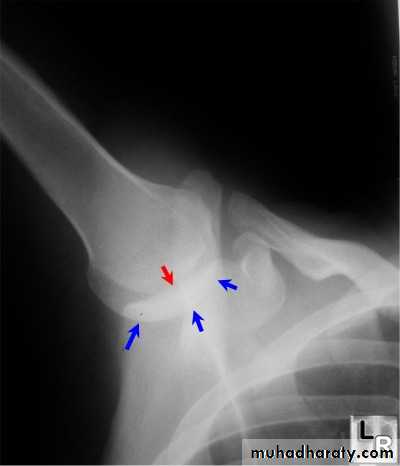

Inferior sholder dislocation (Luxatio erecta): (1-2)%

Luxatio erecta ─ uncommon form of shoulder dislocation.

-Extremity held over head in fixed position with elbow flexed.

- Severe hyperabduction of arm resulting in impingement of humeral head against acromion

-Humeral articular surface faces inferiorly